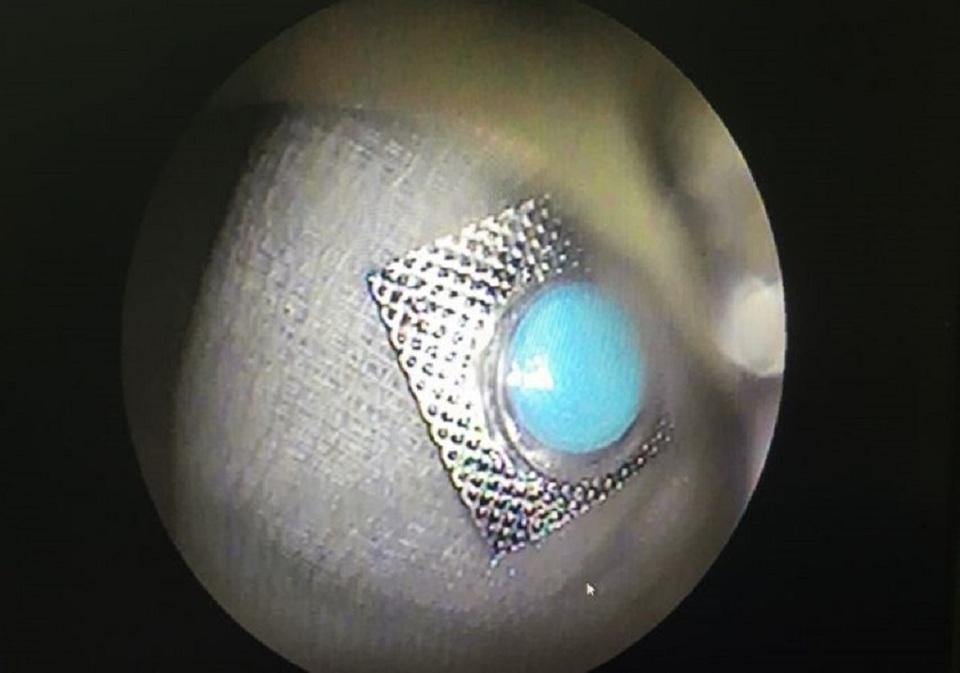

Các bác sĩ nhận định, vết thương thực quản do dị vật gây ra không phức tạp, tuy nhiên rất nguy hiểm, có thể làm thủng thực quản gây nhiễm trùng trung thất, đe dọa tính mạng bệnh nhân. Để tránh rủi ro có thể xảy ra, ê kíp can thiệp đã quyết định gây mê cho bệnh nhân, sử dụng chụp dị vật silicon bao các cạnh sắc nhọn để tránh gây rách thực quản, gắp thành công dị vật có kích thước 9x9mm ra ngoài.